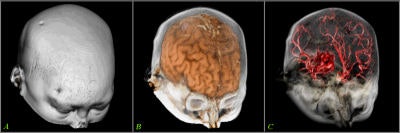

Tomographic examination of pathologies is currently performed by slice-based visual inspection despite the volumetric nature of the anatomical components, tumors/lesions, and imaging modalities. The reason for this could be the radiologist's 2D-based training for distinguishing between normal and abnormal tissue. The introduction of 3D imaging and augmented reality has prompted a huge interest in the utilization of such technology. Virtual endoscopic systems based on perspective rendering have been developed to allow the physician to "fly through" the patient's anatomy. Using such methods, the physician can reduce the opacity of certain tissues (such as the brain) to look at the internal structures (see figure 5, below).

![]() |

| Figure 5 |